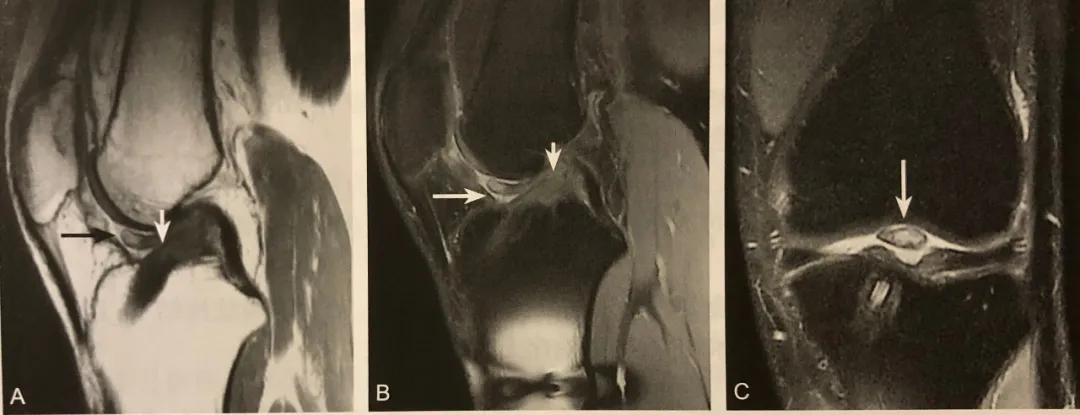

半月板囊肿

A.T2WI 压脂矢状位内侧半月板前角旁见类圆形长 T2 信号影(箭头);

B.T1WI 矢状位病灶呈长 T1 信号(箭头)

C.病灶主要位于半月板前角边缘和关节囊之间(箭头)

半月板囊肿的 MRI 典型表现为半月板外缘与关节囊之间出现的囊性病变,MRI 信号特点为 T1WI 呈稍低或低信号,信号均匀;T2WI 脂肪抑制呈高信号。

阅片要点:

1. 主要位于半月板前角边缘和关节囊之间;

2. 在膝关节侧位片或 MRI 矢状位视察;

3. T1WI 稍低或低信号;

4. T2WI 脂肪抑制呈高信号;

5. 增强扫描病变无强化或边缘轻度强化。